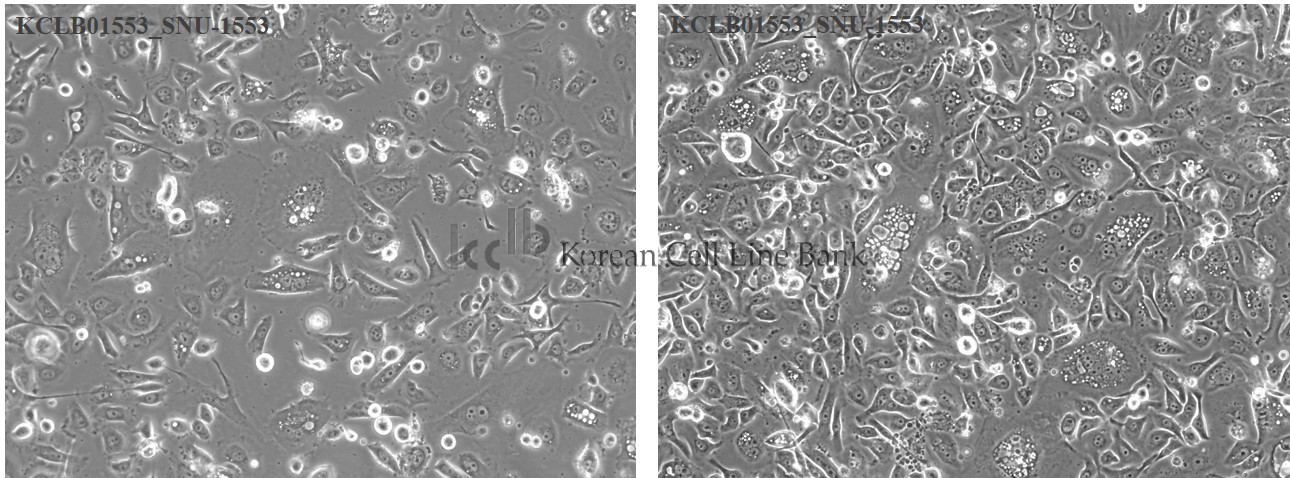

| Cellular morphology |

epithelial

| Growth Pattern |

monolayer

| Histopathology |

breast cancer, Infiltrating ductal carcinoma